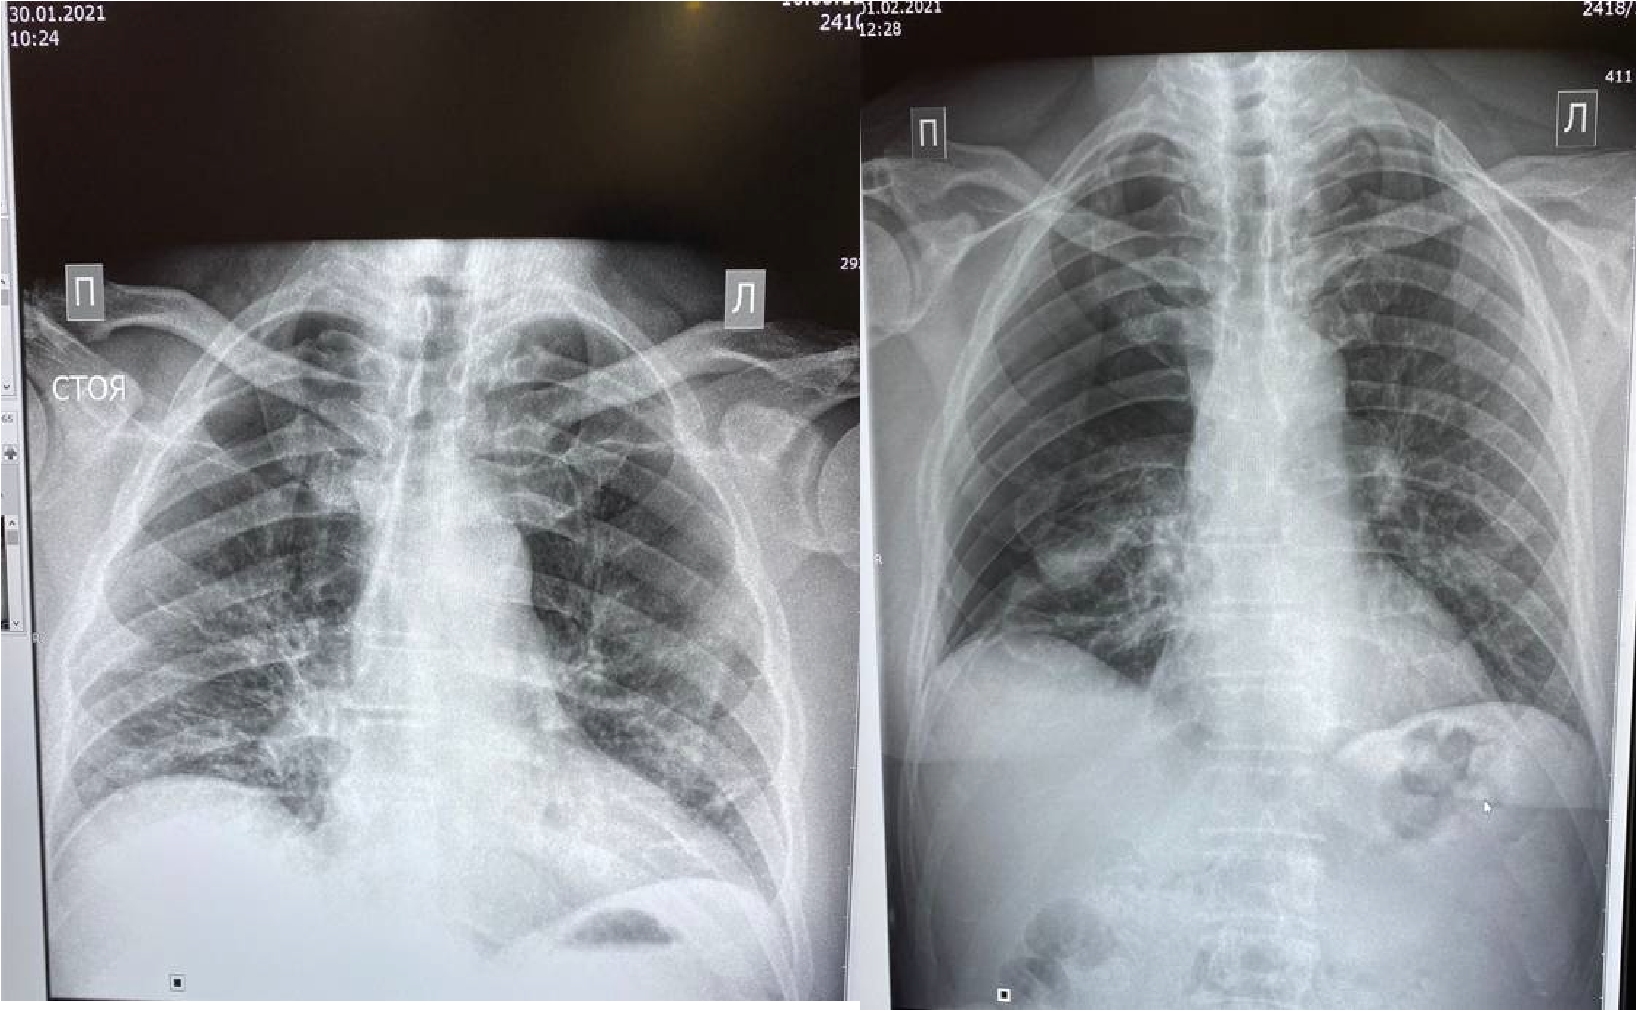

Рисунок 1. МСКТ органов грудной клетки – признаки двусторонней полисегментарной интерстициальной пневмонии (объем поражения 20%, КТ-1).

Пациент (мужчина) 55 лет поступил в стационар с жалобами на сухой кашель, нарушения обоняния и вкуса, одышку при нагрузке, ощущение тяжести в грудной клетке, слабость, боли в мышцах и повышение температуры тела до 380 С. Больной обратился за медицинской помощью на 5 сутки после появления симптомов ОРЗ в связи с неэффективностью самостоятельного лечения и появлением одышки. При поступлении по данным МСКТ легких – признаки двусторонней полисегментарной интерстициальной пневмонии с объемом изменений в пределах 20%, КТ-1 (рис.1). Короновирусная инфекция была подтверждена результатами ПЦР. При поступлении состояние было расценено как средне-тяжелое.